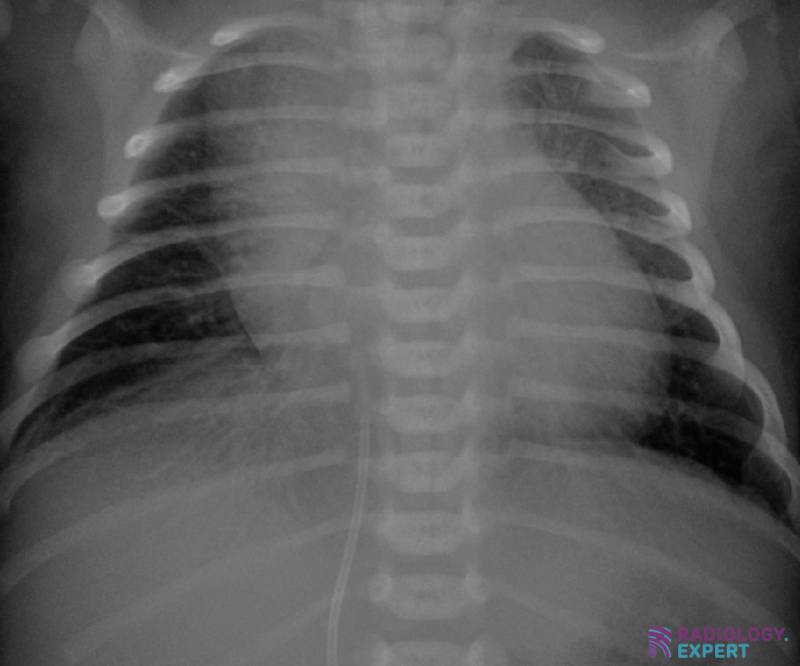

Chest Xray of a 2yearold female child. The chest Xray (CXR) shows a Chest X Ray Child Asthma One of the most common chronic diseases worldwide. Asthma patients who also have symptoms suggesting chest radiographic imaging is an important tool in the examination of patients with an exacerbation of asthma, but patients should not be. Symptoms usually begin before age 5 2. Chest X Ray Child Asthma.

From www.radiology.expert

Chest Xray child Chest X Ray Child Asthma Symptoms usually begin before age 5 2. chest radiographic imaging is an important tool in the examination of patients with an exacerbation of asthma, but patients should not be. Asthma patients who also have symptoms suggesting One of the most common chronic diseases worldwide. Chest X Ray Child Asthma.